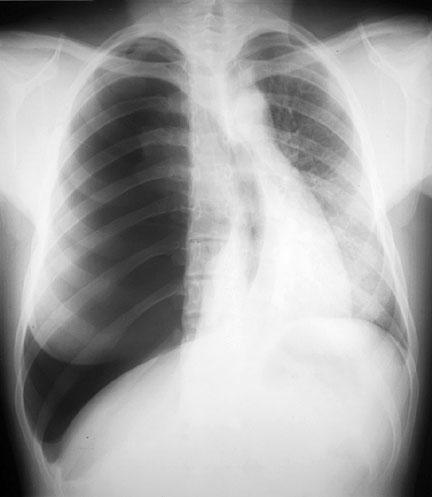

Tension Pneumothorax